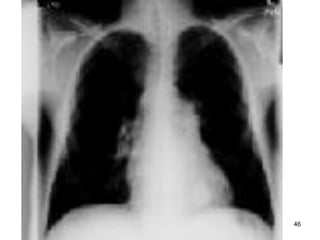

Chaån Đoaùn

Coù hình aûnh ñaëc tröng giuùp Δ() , nhöng khoâng ñeå Δ(+)

 Khí pheá thuõng, taêng thaâm nhieãm, cô hoaønh deït, tim

heïp,  tröôùc sau cuoáng phoåi, môû roäng khoaûng khoâng

sau xöông öùc (ÑM ôû trung taâm roäng hôn do taêng aùp ôû phoåi).

→ Khí pheá thuõng aûnh höôûng tôùi ñaùy phoåi, taêng saùng

ñeán maát nhu moâ

 Taêng goùc xöông öùc & tröôùc cô hoaønh.

 Daáu PQ-MM

 Thaát phaûi lôùn (beänh lyù tim-phoåi)

 CT scan ñaùnh giaù cöôøng ñoä vaø phaân boá khí pheá thuõng,

caùc baát thöôøng khaùc.